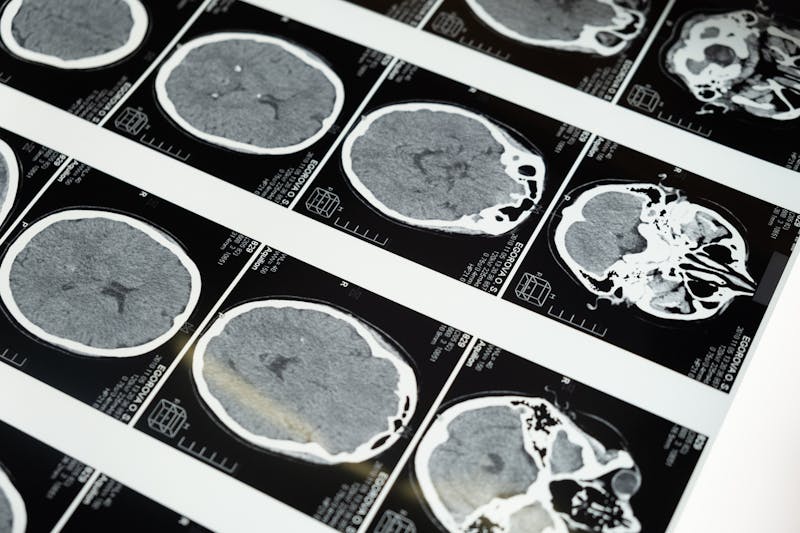

L'IRM cérébrale (Imagerie par Résonance Magnétique) est une technique d'imagerie cérébrale non invasive qui utilise un puissant champ magnétique et des ondes radiofréquence pour produire des images très détaillées du cerveau et des structures intracrâniennes.

Contrairement au scanner (tomodensitométrie), l'IRM n'utilise pas de rayons X. C'est un examen totalement indolore et sans irradiation, ce qui le rend particulièrement adapté à l'exploration neurologique, y compris chez les enfants.

Les différentes séquences IRM (T1, T2, FLAIR, diffusion, perfusion) permettent d'analyser la structure du cerveau sous de multiples angles, révélant des anomalies invisibles avec d'autres techniques d'imagerie.

L'IRM cérébrale est un examen d'imagerie médicale essentiel, reconnu comme la technique de référence pour explorer le cerveau et ses structures. Indolore, sans irradiation et très bien tolérée, elle permet de diagnostiquer avec précision un large éventail de pathologies neurologiques, des céphalées chroniques aux tumeurs cérébrales, en passant par la sclérose en plaques ou les accidents vasculaires cérébraux.